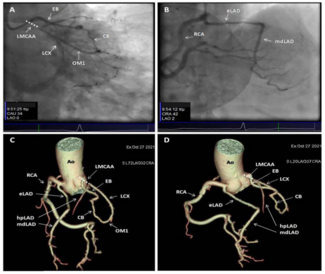

A 75-year-old woman was referred to our center for coronary angiography (CA) due to atypical chest discomfort unrelated to exertion and accompanying coronary artery disease risk factors (hypertension, type 2 diabetes, former smoker). CA was...